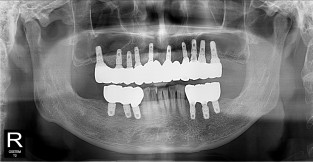

풀케이스

치료기간 : 2022-03-18 ~ 2023-09-15

1. 상기 x-ray 이미지 모두 동일한 해당 의료기관에서 진료한 환자입니다.

2. 상기 x-ray 이미지 모두 동일 인물의 것입니다.

3. 치료 전 이미지는 2022-03-18에 촬영했으며, 치료 후 이미지는 2023-09-15에 촬영하였습니다.

4. 상기 x-ray 이미지 모두 동일 조건에서 환자분의 동의를 받아촬영되었습니다.

* 임플란트 시술은 환자분의 상태(고혈압, 당뇨 등)에 따라 부작용이 있을 수 있으니, 반드시 전문의와 상담이 필요합니다.

* 임플란트 수술 부작용

: 수술 후 출혈, 교합, 통증, 붓기, 염증 등의 문제점이 발생할 수 있습니다.)